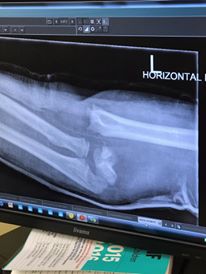

在10歲時,因練習摔斷了骨頭

(British champion for his age) but broke his arm very badly last year. This

paralysed for three months with nerve damage. It’s amazing what great

doctors and a dedicated physio can do." (請忽略文法/拼字錯誤)

三個月的神經麻痹啊!!! 這個小小孩是怎麼撐過來的?